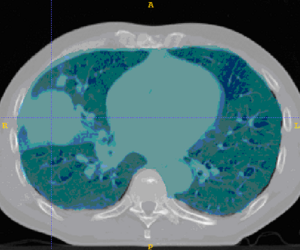

This example shows anatomic change in the thorax. The patient has a collapsed left lower lobe in the pre-treatment scan (top), which has recovered in the mid-treatment scan (bottom). Notice there is some kind of fluid accumulation below the collapsed lung.

Below are examples of segmentations of targets and critical structures for head and neck, and thorax. These structures (or similar) would be manually delineated for every patient who gets 3D planning.